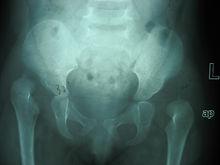

3.X檢查

更適合6個月以上者,不建議對3個月以內者進行X線檢查。拍攝髖關節正位片要求患兒安靜,下肢與肩同寬,腳尖向內鏇轉20°左右。DDH患兒的X線表現有髖臼指數增大、沈通氏線中斷、正常股骨頭骨化中心不位於由Hilgenreiner和Perkins線所構成方格的內下1/4象限內。髖臼指數隨年齡的增大而變小,2歲時應該在24°以內。小於8歲兒童,髖臼指數是測量髖臼發育的可靠指標。當患兒大於5歲,測量CE角的價值大,在成人患者,則是最有用的指標之一。當Y形軟骨閉合後,Sharp髖臼角也是測量髖臼發育不良的有用指標。

發育性髖關節發育不良正常髖關節

發育性髖關節發育不良雙側髖關節脫位